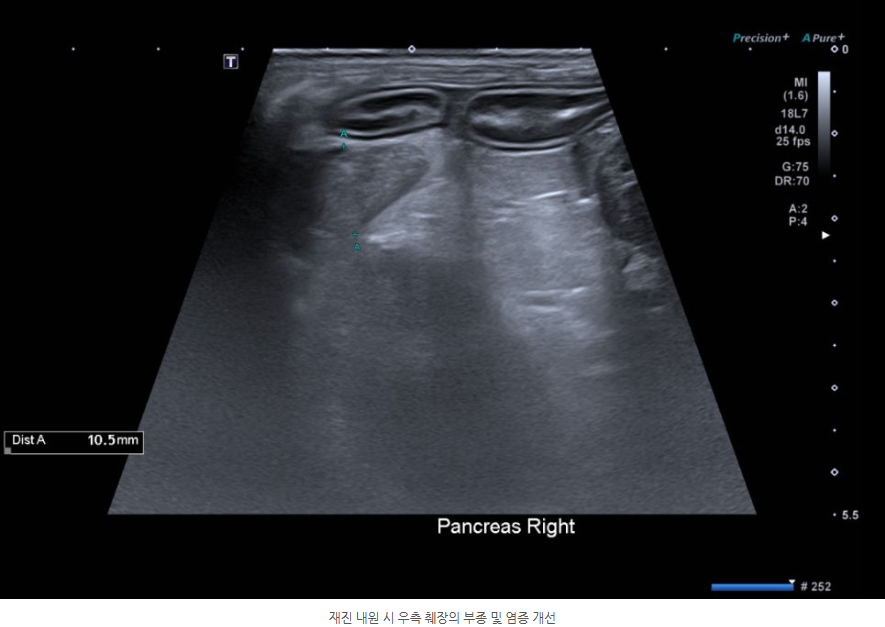

재진 내원 시 대다수의 혈액검사 수치 개선이 확인되었으며 복부초음파상 확인되던 부종성 병변과 염증소견은 현저한 개선을 보였습니다.